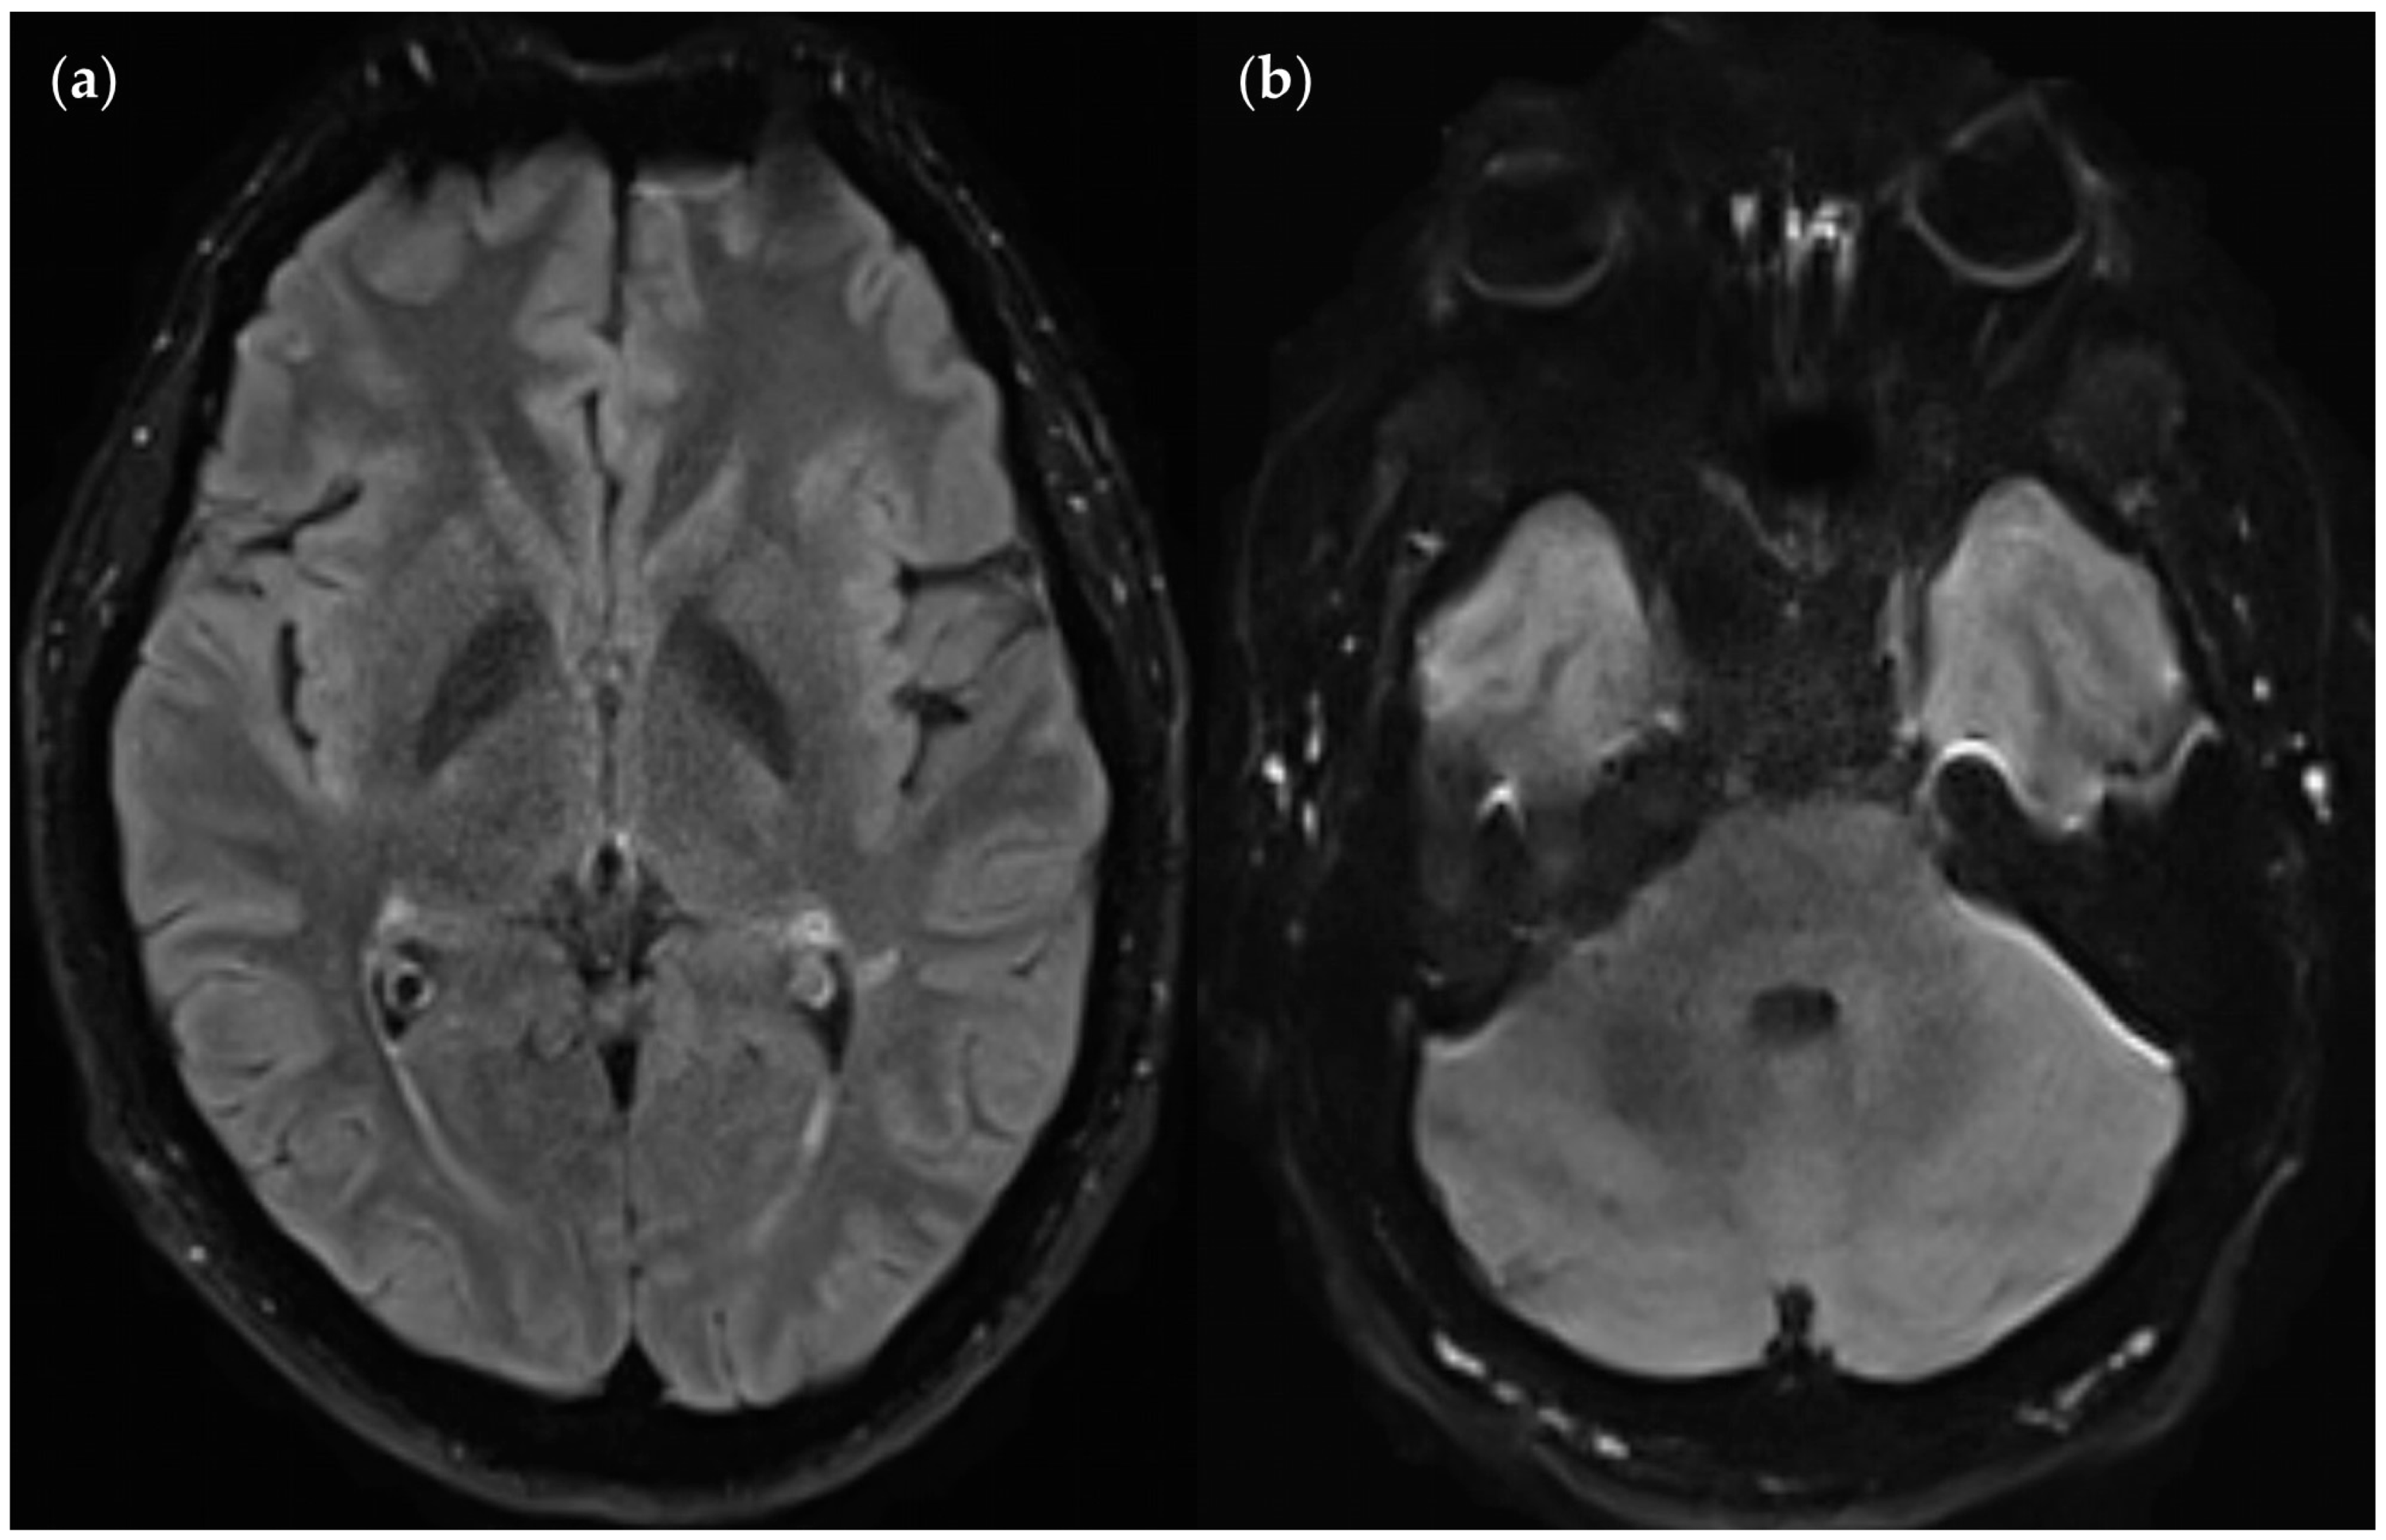

3.2.3. Dependence on Size and Location within FLAIRUF

3.3.3. Positional Dependence of SNR and CNR in FLAIRUF

4.3. Limitations of the FLAIRUF Images

4.4. Considerations on Ratings for Lesion Conspicuity in FLAIRUF

4.5. Outcomes Correlated with Technical Features